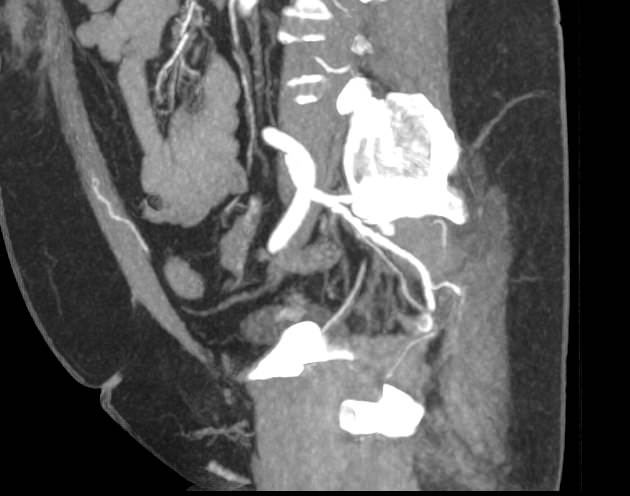

При нативной КТ кровеносные сосуды не видны. Поэтому, чтобы детально визуализировать сосудистую систему, обязательно проводится контрастное усиление. Для этого в периферическую вену пациенту вводится контрастный препарат, который попадая в кровеносное русло, поглощает рентгеновские лучи и ярко контрастирует сосудистую систему малого таза. В результате получаются детализированные снимки кровоснабжения внутренних половых органов, мочевого пузыря, прямой кишки.

На снимках КТ-ангиографии с контрастированием четко видна брюшная аорта, место ее разветвления на подвздошные артерии (бифуркация), а также сосудистые ветви, отходящие к органам малого таза. Снимки и 3D-изображения позволяют оценить: